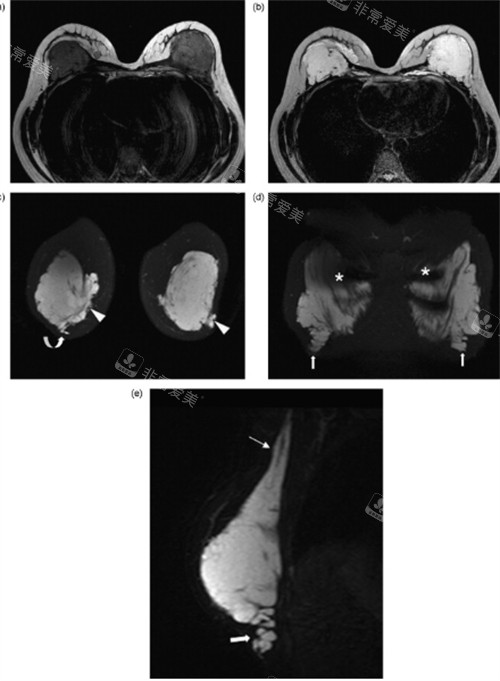

有胸部取奥美定加假体植入需求者,核心想知晓2026年该项目的具体收费区间、分级定价标准及不同假体搭配的费用差异,也关注特殊临床情况的附加收费。本文将结合奥美定取出难度分级,给出2026年不同假体材质搭配的详细收费参考,解析影响价格浮动的核心因素,非常爱美网400-660-1985,为求美者提供贴合实际的费用参考依据。

2026年胸部取奥美定的基础费用,核心依据奥美定扩散分级制定,结合临床操作中是否采用内窥镜小创伤取奥技术,形成清晰的基础定价梯度,这也是取奥美定加假体整体费用的核心组成部分。不同扩散程度的奥美定,取出时的组织剥离难度、操作时长差异显著,费用自然形成分层。

轻度奥美定取出为注射物局部聚集在脂肪层,无扩散无粘连,采用内窥镜小创伤技术即可完成,基础取出费用划定为核心基准。中度奥美定取出为注射物弥散至胸肌浅层,伴随轻微包膜形成,需联合包膜切除操作,基础费用随操作难度上浮。

重度奥美定取出为注射物扩散至胸肌深层甚至腋窝,伴随组织粘连或轻度炎症,需先做清创处理再精又准取奥,基础费用为三阶梯度中更高。该分级定价均包含麻醉费、术中耗材费及基础腔隙修复费,无常规隐形收费。